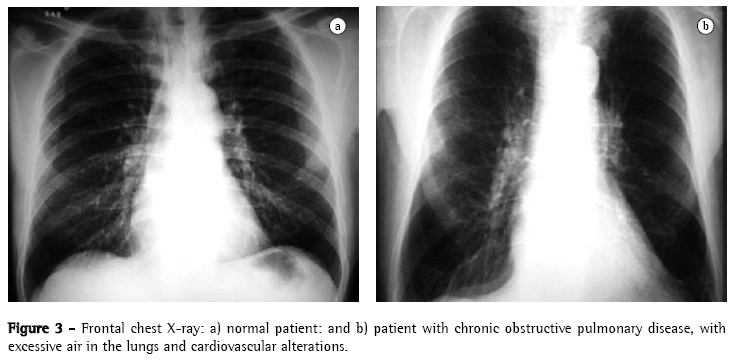

The yield of conventional chest X-ray in the evaluation of emphysema is quite limited. When there is no significant air trapping, the principal alteration is reduction of vasculature, which is only perceived too late in the natural history of the disease, and is an extremely subjective criterion. When there is air trapping (Figures 3 and 4), the criteria are safer, and can be divided into 3 basic groups of alterations,(6,8) presented in Chart 1. When all criteria are present, the diagnosis is definitively confirmed. It should be noted that the increased right chambers of the heart, with reduction of the intrasegmental vasculature, can also be identified in pulmonary arterial hypertension, without emphysema. It should also be noted that bullae are only present in approximately one-third of the cases.

One author comments that the emphysematous pattern defined by the conventional radiological study is only present when the emphysema is so pronounced from the anatomopathological point of view that, in general, pulmonary reserves have already been depleted or pushed to the limit (6,8) A more updated review(22) confirms these propositions:

"If the lungs are mildly affected by emphysema, the X-ray is frequently normal";

"Emphysema can be diagnosed by X-ray when the disease is advanced"; and

"Only half of the patients with emphysema of moderate extent can be diagnosed by chest X-ray."

Both authors suggest that conventional chest X-ray is not a reliable method for the diagnosis or quantification of emphysema.(22) This limitation is so significant that some authors(21) demonstrated that, when conventional radiology managed to diagnose chronic obstructive pulmonary disease, 53% of the patients died within 5 years, and 70% died within 10 years.